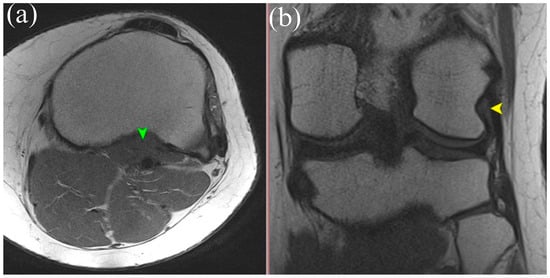

MRI is the gold standard for evaluating soft tissue structures in the knee, including the PT. Optimal visualization of the tendon is achieved using T1 and T2 weighted sequences (Figure 1 and Figure 2) with fat saturation in axial, coronal, and sagittal planes. The PT appears as a low signal intensity structure running obliquely from the lateral femoral condyle to the posteromedial tibia [1,15].

Figure 2.

(a) Axial T1-weighted MRI showing the muscle belly of the popliteus muscle (green arrowhead). (b) Coronal T2-weighted MRI illustrating the tendinous portion of the popliteus (yellow arrowhead). Both panels demonstrate anatomical relationships of the popliteus tendon complex relevant for imaging-based identification.

Particular attention must be given to morphological variations. The presence of bifid tendons or accessory bands (Types II–IV according to Olewnik’s classification) can be mistaken for tendon ruptures, scar tissue, or pathological adhesions [11]. Recognition of these variants is essential to avoid misdiagnosis.

In acute traumatic cases, key findings include hyperintensity within the tendon on T2 weighted images, peritendinous fluid, discontinuity of tendon fibers, and surrounding soft tissue edema [1]. MRI can also reveal the secondary signs of PT injury, such as displacement of the lateral meniscus, stretching of the fibular collateral ligament, and abnormal tibial rotation [15]. Studies have shown that awareness and identification of the anatomical variability of the PT during MRI interpretation of acute knee injuries can improve diagnostic sensitivity and specificity by 15–20% [6].